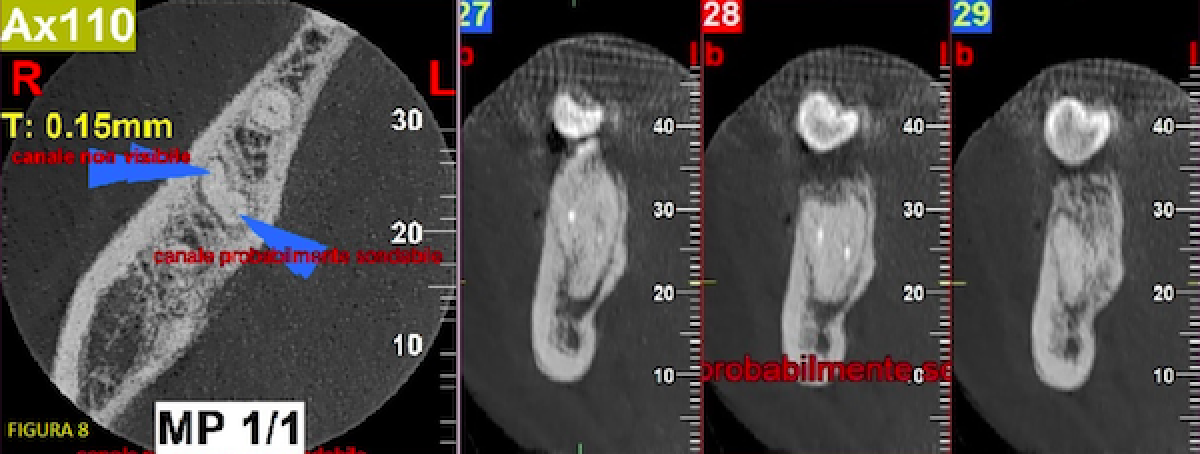

Extensive, expert use of the software highlighted the presence of a patent canal as far as the apex in the medial root with a small radio-opaque area that could not be identified (broken instrument? cement?). Nevertheless, the possibility of being able to overcome the obstacle could be glimpsed.

The other two canals were not apically detectable at the end of the existing root canal fillings (fig. 8).